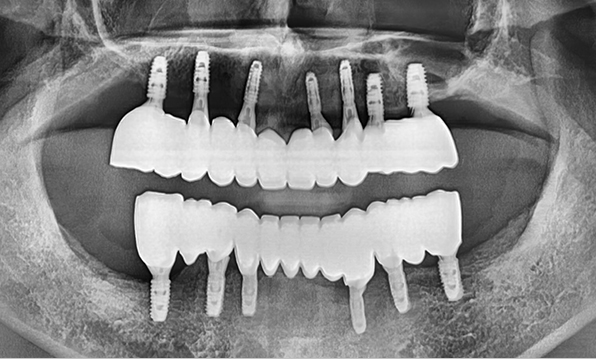

Using a method of placing 8–9 implants in the maxilla and 8 implants in the mandible, this approach fully restores all 28 natural teeth, creating an oral environment most closely resembling

natural dentition.

Using a method of placing 6–7 implants in the maxilla and 6 in the mandible, this approach restores both posterior and anterior teeth, efficiently rehabilitating the entire oral cavity.

Case 04

Before After